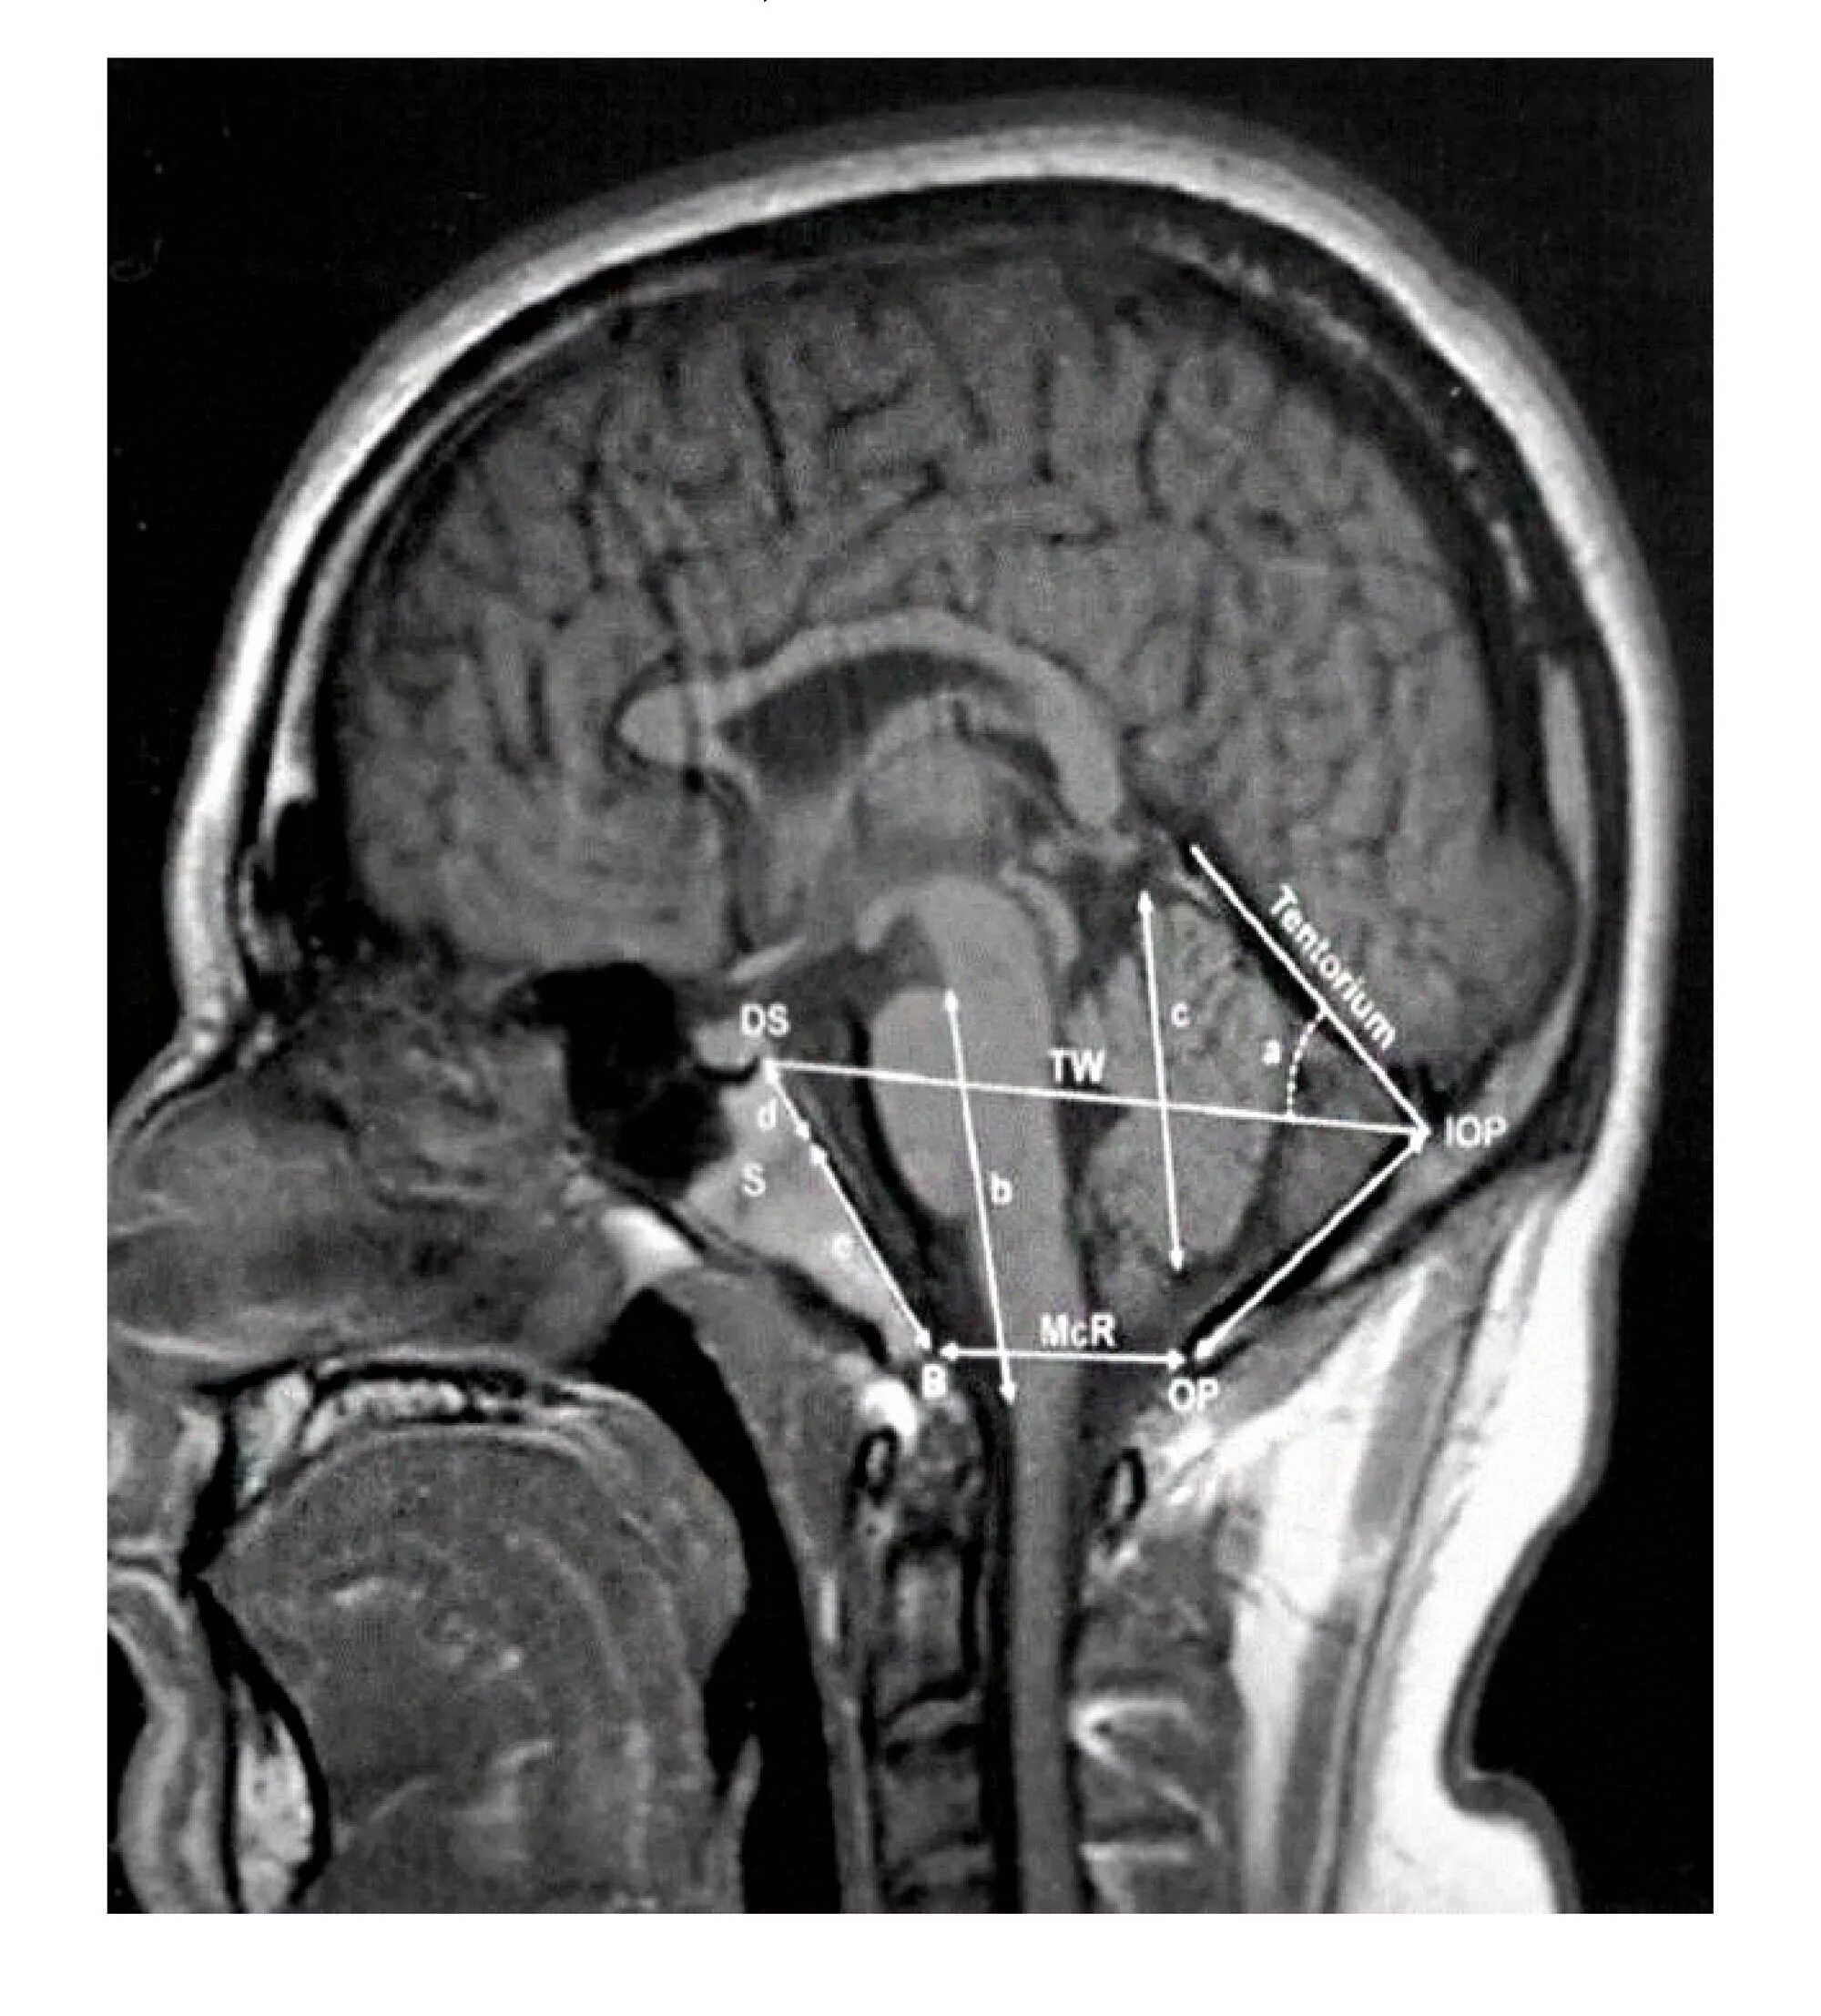

Пролабирование мозжечка